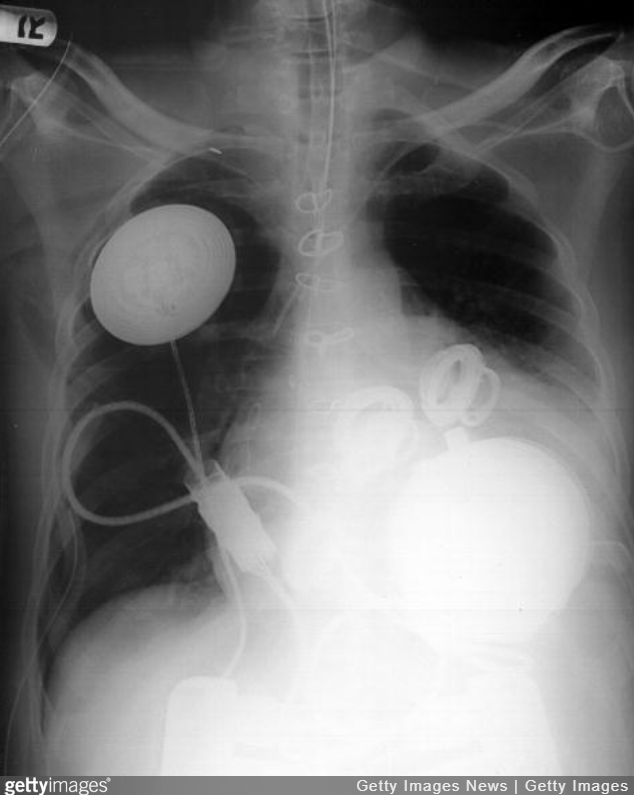

#2. The aorta is the biggest artery in our body.